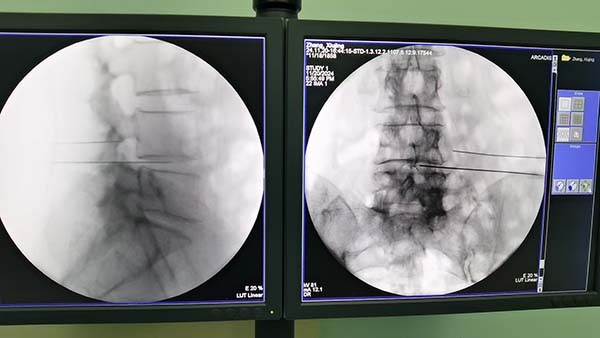

科室常规开展脊神经和周围神经射频消融术、富血小板血浆注射术、臭氧治疗术、三叉神经微球囊压迫术,星状神经节阻滞镇痛术、腰交感神经和腹腔神经丛毁损术、脊髓电刺激器植入术、鞘内吗啡泵植入术等特色微创治疗技术。

目前,疼痛科涵盖本部、常营、石景山三个院区,有疼痛门诊5间、疼痛治疗室3间,疼痛病床16张。疼痛门诊治疗室常规开展有创注射治疗、冲击波治疗、偏振光治疗、毫米波治疗等。目前年门诊量超过2万人次,门诊治疗量有创4000余例、无创5000余例。近年疼痛科飞速发展,每月收住顽固疑难疼痛患者及完成影像引导下介入手术近三百例,年均可达数千例。疼痛病房日间病区收治一日手术患者,住院病区收治三级四级手术患者。疼痛科拥有便携超声4台、C形臂X光机2台,以充分保障微创介入手术的顺利开展。